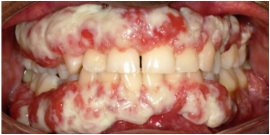

Oral involvement is a common manifestation of PLGD-1 with 32% of patients impacted by these thick, nodular masses on the gums with a distinctly hard, "woody" texture. This condition is known as periodontal disease, ligneous periodontitis, or ligneous gingivitis.1,9,10

With ligneous gingivitis, the gingiva often looks swollen, thickened, firm, and pale, with a characteristic yellowish-white color. Chronic irritation from fibrin deposits and ongoing inflammation can make the gums bleed easily. Over time, persistent fibrin accumulation and inflammation may destroy periodontal tissues, resulting in tooth loss and resorption of the surrounding bone.9,10

Review the lesion image gallery for more examples of ligneous gingivitis.

Ligneous gingivitis caused by congenital plasminogen deficiency type 1, manifesting as gum lesions